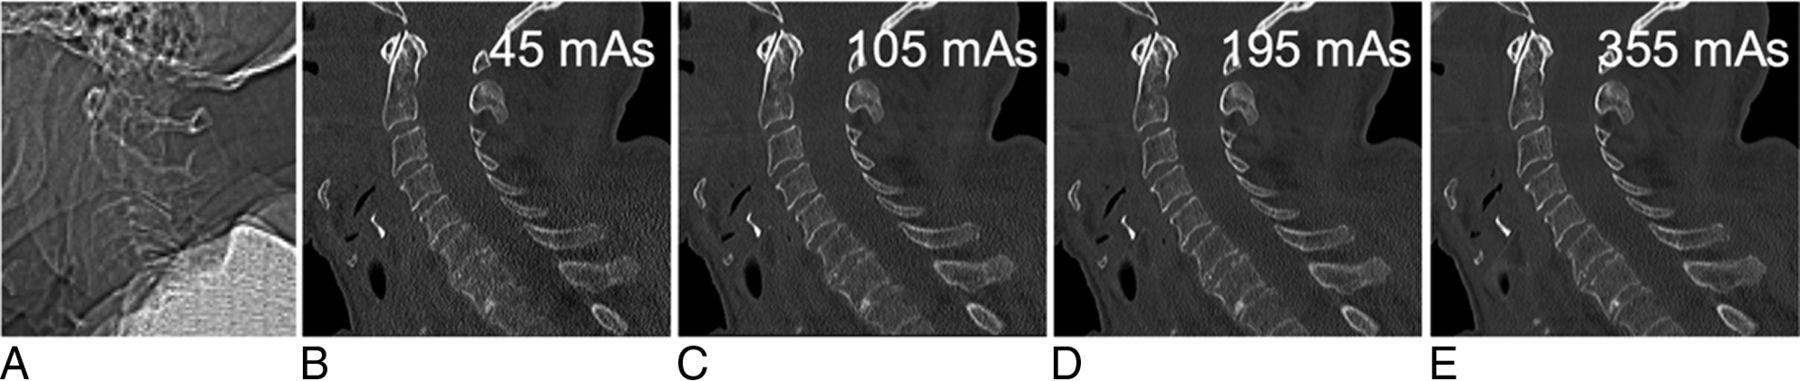

Four circular ROIs of 100 mm2 each at the cervical spine levels (C1–2, C3–4, C5–6, and C7–T1) served for noise measurements. They were placed in the extracorporeal air on axial images at exactly the same level in each scan of the same cadaver by 1 reader with 2 years of experience in spine imaging (Fig 2). Image noise was defined as the SD of the mean CT numbers measured in Hounsfield units within an ROI.

Quantitative and qualitative image noise were evaluated on 4 different cervical spine levels (A, dashed lines). Axial image (B) at level C5–6 shows 4 ROIs of 100 mm2 each in the extracorporeal air for quantitative noise measurements.

All CT images were displayed with the window level/width set to 600/2000. A total of 72 datasets were assessed using axial and sagittal reformations in OsiriX, Version 4.1.2 (http://www.osirix-viewer.com). Qualitative image noise was graded on a 3-point scale (1 = no noise, 2 = acceptable minor noise, 3 = unacceptable major noise) on 4 levels: C1–2, C3–4, C5–6, and C7–T1 using sagittal reformations (Figs 2A and 3). Morphologic characteristics of the bony structures were analyzed on a Likert scale. On each cervical segment (eg, C3), the cortex, trabeculae, and integrity of the anterior and posterior vertebral body lines were assessed; on each cervical level (eg, C3–4), alignment was assessed on either a 2- or a 3-point scale as shown in Table 2.